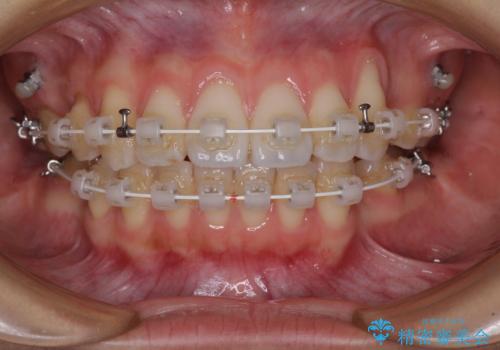

- 審美装置

- 1年11ヶ月

- 八重歯と口元の突出感を気にして来院された患者様です。

歯列が前方に突出しており、上下の正中がズレていたため、左側は上下第一小臼歯を、右側は上下第二小臼歯を抜去し、ワイヤー装置による矯正治療を行うこととしました。

当初はインビザラインによる矯正治療をご希望でしたが、正中を合わせたいことや、口元の突出感を改善したいことから、ワイヤー矯正を強く推奨しました。

治療期間は2年に満たず、スッキリとした口元に仕上がりました。